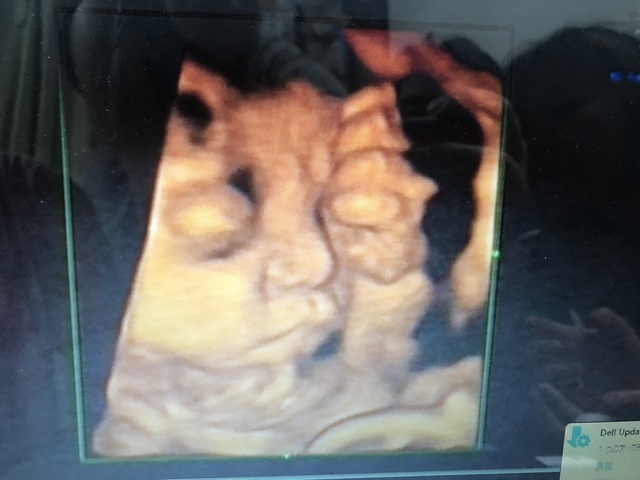

35週6日(35w6d・男の子)|ちゃさ さん(24歳)

エコー写真撮影時のエピソード:

いつも3Dまでしか見れないんですが、お金を払えば4Dが見れるということで撮りましたーっ^_^すごい鮮明に見えて、この時点でどっち似かわかるくらいです!!いろんな表情も見れてよかったですっ(●´ω`●)♬

これわ絶対撮るべきだと思いますよ〜〜!!!!!!!